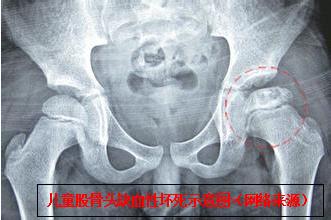

骨伤六科副主任中医师陈凯奇当时正在休假,接到该患儿外伤病例电话邀诊后,立即组织该团队主治医师陈宏慈和医护人员启动假日接诊预案,进入相关接诊诊疗工作程序。患儿16时45分送达骨伤六科诊室,当时烦躁、哭闹不止。医疗团队快速、专业地开展诊治流程,经检查发现,幼儿左下肢短缩、屈曲、内收、内旋畸形,弹性固定,活动受限,于患侧髋臀肌部可触及隆起。再详细查阅外院X光片,结合幼儿遭遇外力撞击的情况,确诊为:左髋关节脱位(后脱位)。

经过2分钟的中医正骨手法治疗后,下午17时35分,患儿复查X光检查结果出来了,骨伤六科医疗团队看到幼儿左髋关节脱位复位后关节位置结构正常,如释重负地松了一口气。

儿童创伤性髋关节脱位(traumatic dislocation of the hip in children,TDHC)发生率较低,临床甚为少见,年龄越小发生率越低。据相关文献报道,TDHC占所有髋关节脱位的5%~10 %,TDHC患儿一般在5岁以上,3岁幼儿病例报道基本罕见。如不能及时明确诊断及治疗,极易导致疗效欠佳及存留后遗症,严重影响患儿成长发育及日后功能活动。

该团队相关负责人介绍,该患儿如不及时快速准确将脱位的髋关节整复,会引发并发症,进而导致股骨头缺血性坏死、髋关节生长紊乱、神经损伤、复发性脱位、创伤后骨关节炎、骨化性肌炎、股骨头创伤性分离。而其中最危急,要与时间赛跑的就是股骨头缺血性坏死,所以,必须在伤后24 小时内完成脱位髋关节的复位。